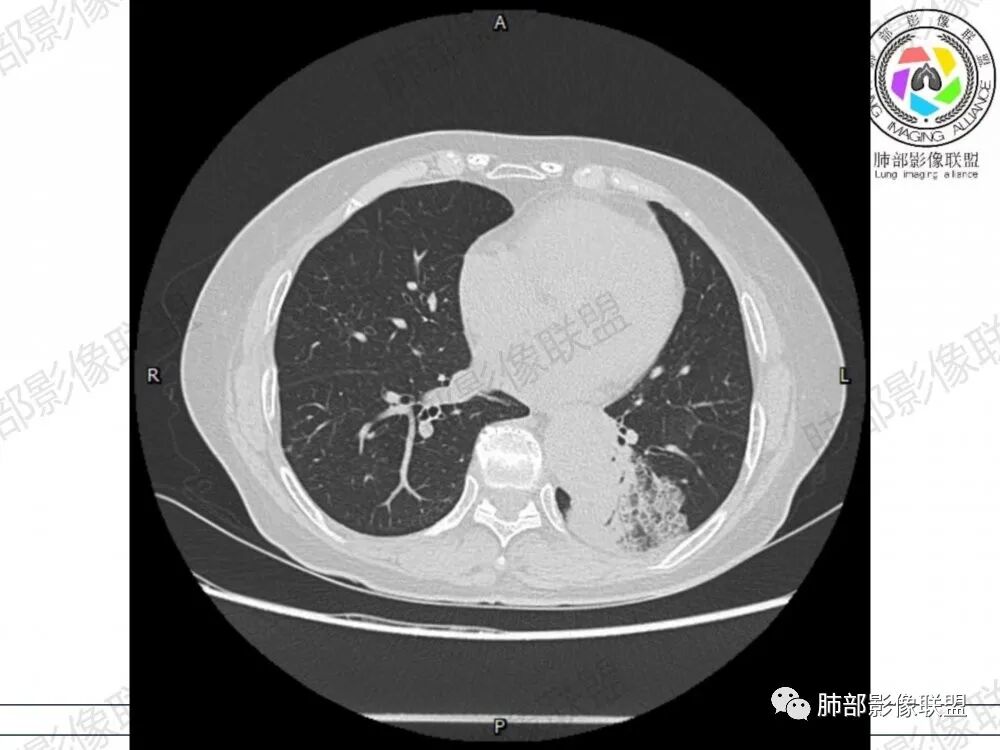

左肺下叶胸膜下混合磨玻璃影,磨玻璃边界清晰,支气管进入后堵塞,增强轻中度强化,无明显坏死空洞。

晨读:左肺下叶胸膜下实性高密度影,部分伴有网格样增厚,内部可见小空泡,壁光滑,周围伴有磨玻璃影,边界清,近端可见支气管穿行,远端支气管堵塞,胸膜下脂肪间隙可见,病变整体收缩,部分有彭隆,增强后可见血管穿行,强化尚均匀。

左肺下叶实变及磨玻璃影,宽基底与胸膜相远,磨玻璃边界清晰,边缘膨隆,病变内近端支气管堵塞,不均匀强化,可见血管影,考虑腺癌,鉴别结核

胸CT:左下叶胸膜下大片斑片影,长轴沿胸膜分布,实变、GGO混杂,磨玻璃边界清晰,粘液密度,小叶内间隔增厚,支气管进入后堵塞(枯枝),增强轻中度强化,血管造影征。常规考虑:肺腺癌?淋巴瘤?鉴别不典型病原体感染。

2、影像表现:无肺气肿背景,病变定位于左肺下叶背内侧基底段,病灶呈不规则团块影,靠近胸膜侧,其内密度不均匀,内见空洞、实变及磨玻璃影,磨玻璃影呈碎石路征,边界清楚,实性肿块边界膨隆,其内见空洞。空洞周围比较实。病灶较大的支气管通畅,细小的支气管成“枯枝征”。无胸膜增厚及胸膜腔积液,增强扫描呈中度强化,见血管造影征。